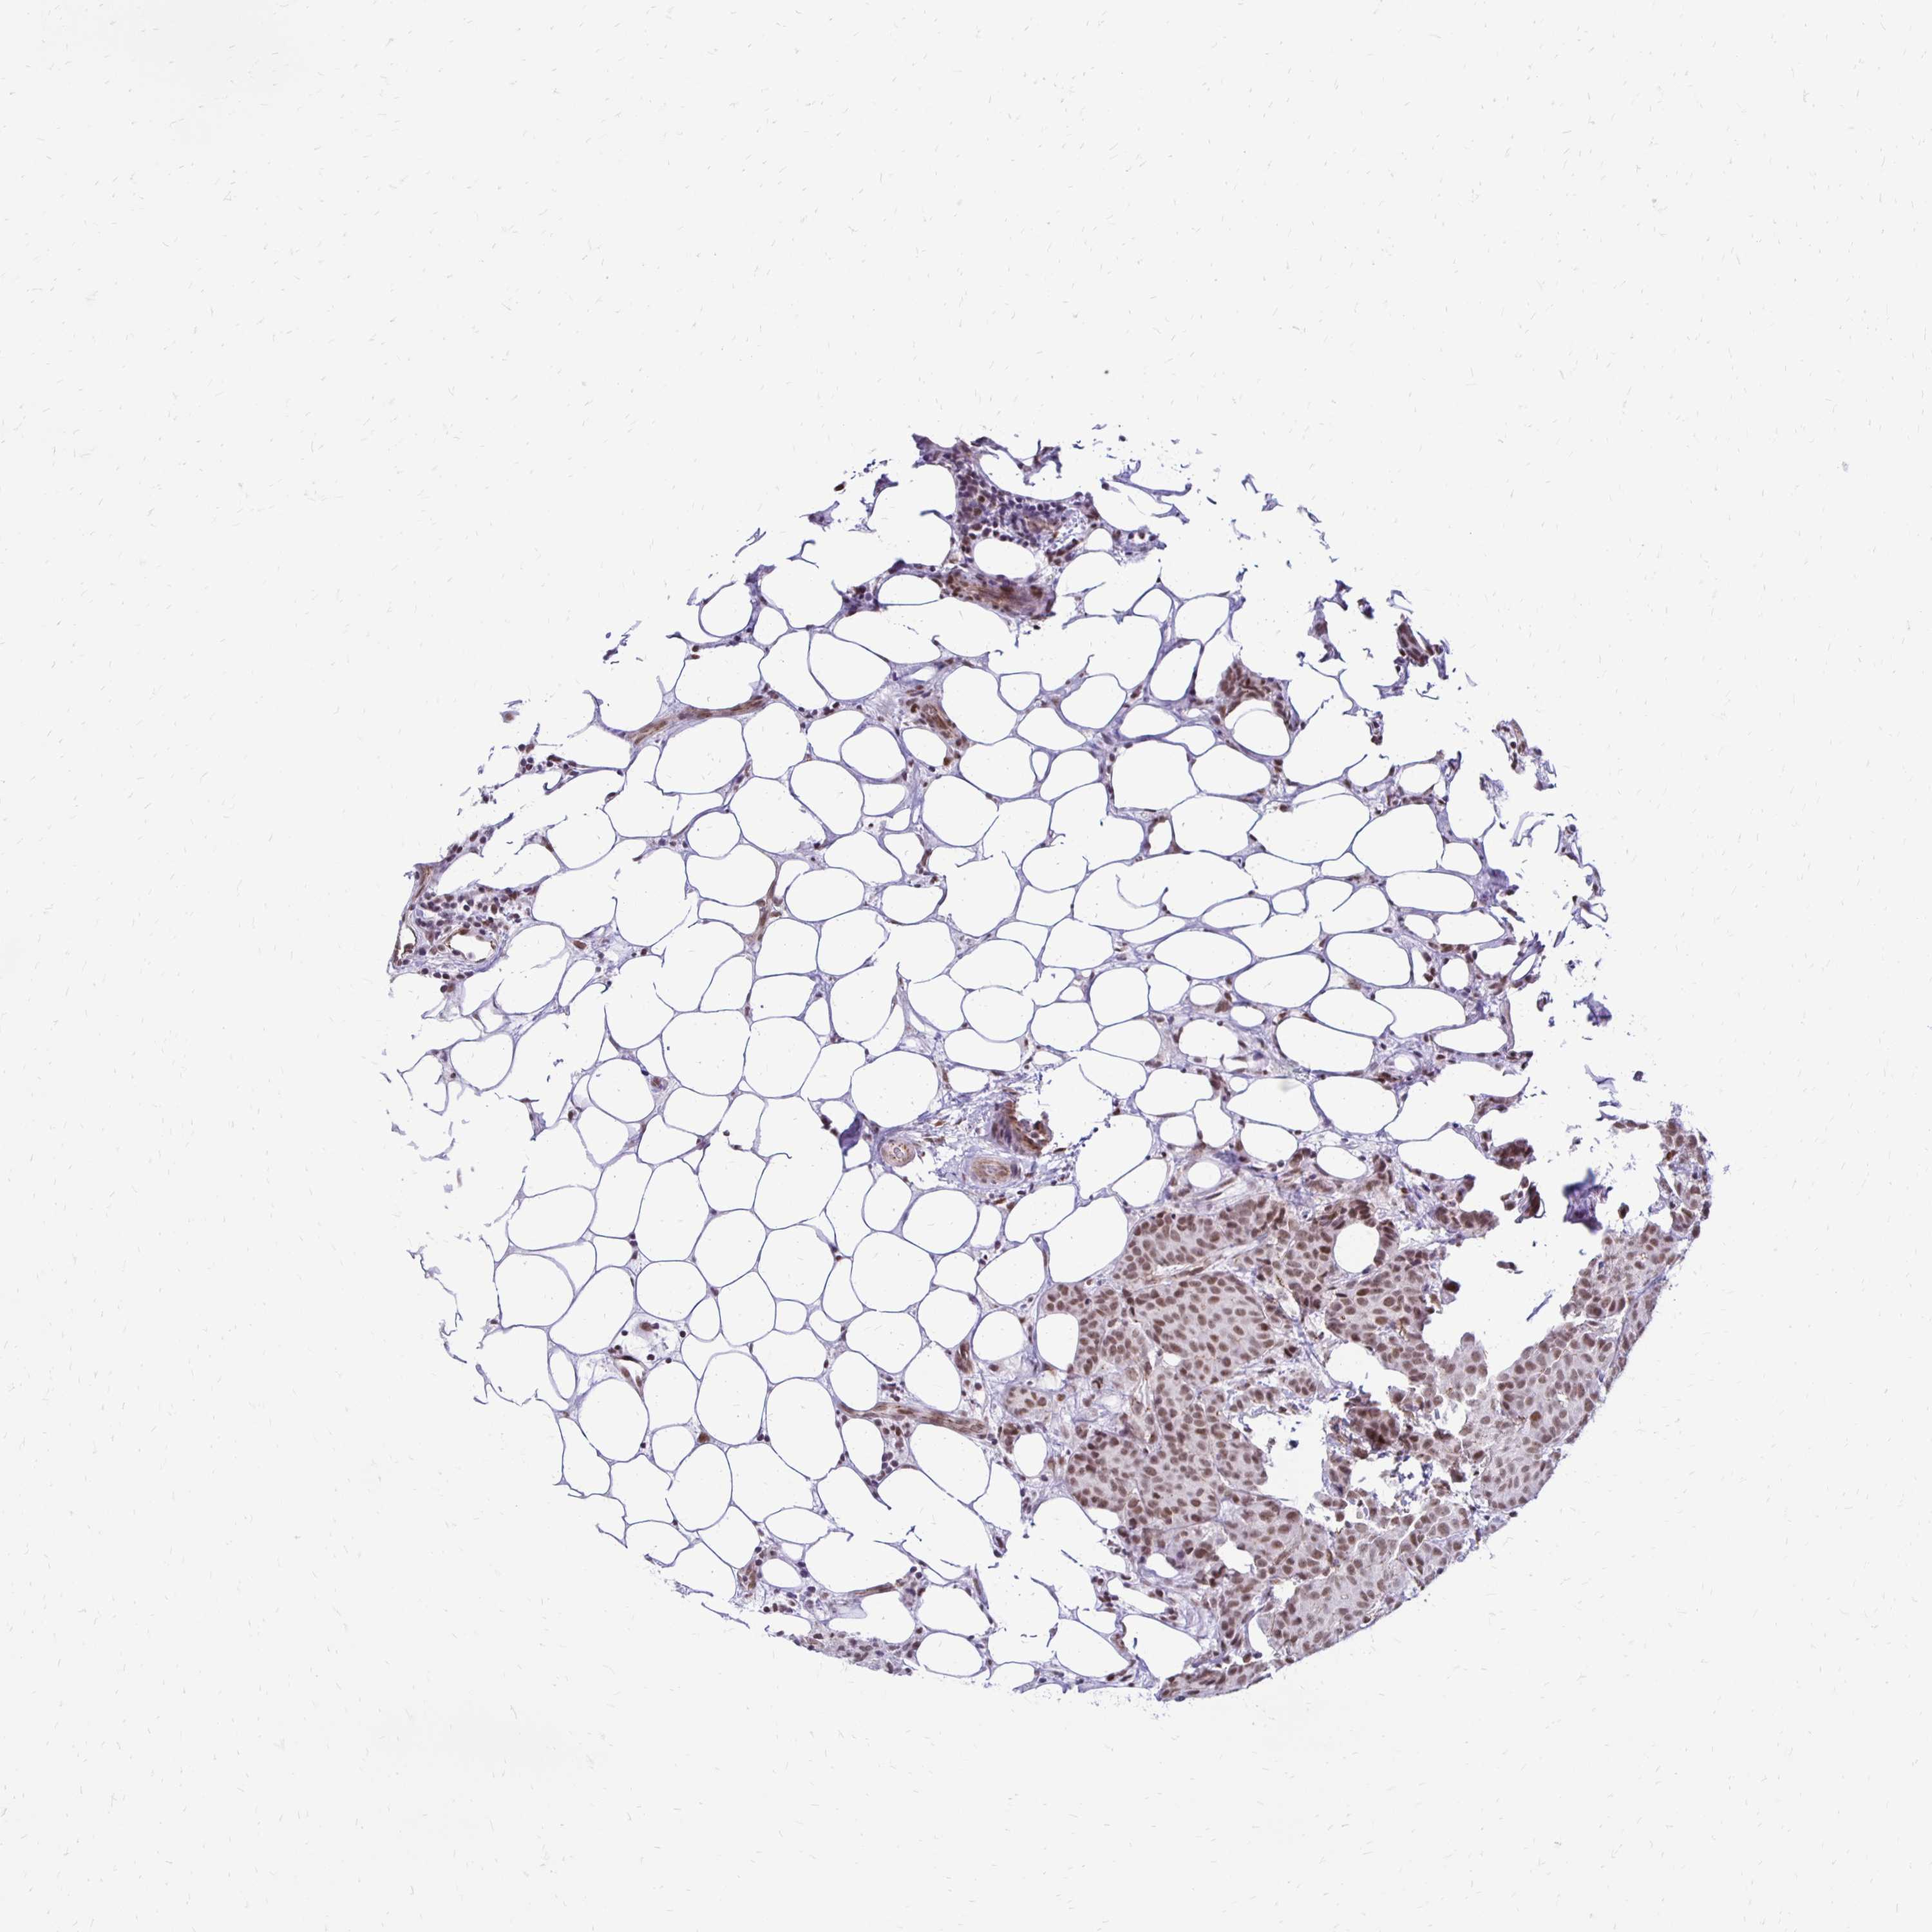

BRCA TCGA BRCA VALIDATION PROTEIN EXPRESSION